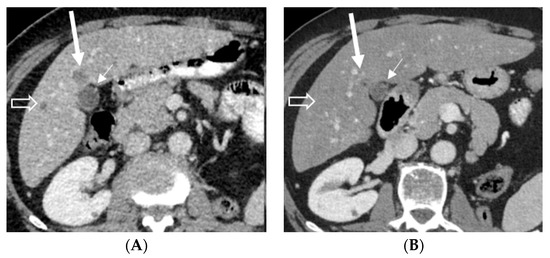

2.1. Case 1